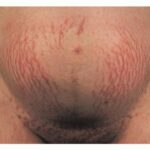

During puberty, striae appear in areas where there is a rapid increase in size. In girls, the most common sites are the breasts, thighs, hips, and buttocks, whereas in boys, they are seen on the shoulders, lumbosacral region, and thighs. Other less common sites include the abdomen, upper arms, neck, and axillae.

Striae distensae are a common finding on the abdomen, and less so the breasts and thighs, of pregnant women, especially during the last trimester. They are more common in younger primigravidas than in older pregnant women. Striae gravidarum can be associated with a higher risk of lacerations during vaginal delivery.23

Striae are usually multiple, symmetric, well-defined linear atrophic lesions that follow the lines of cleavage. Initially, striae appear as red-to-violaceous elevated lines (striae rubra) . Over time, the color gradually fades, and the lesions become atrophic, with the skin surface exhibiting a fine, white, wrinkled appearance (striae alba). The striae can measure several centimeters in length and a few millimeters to a few centimeters in width. The striae associated with systemic corticosteroid therapy and Cushing syndrome can be larger and more widely distributed.